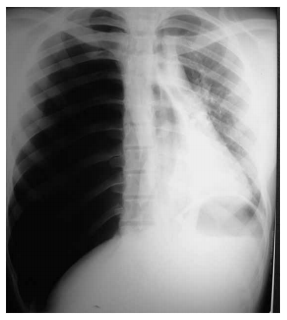

Paciente portador de asma brônquica é trazido por familiares ao pronto atendimento com queixa de dispneia súbita, dor torácica em hemitórax direito e dificuldade para falar. O exame físico revela o paciente sonolento, torporoso, taquidispneico e com cianose de extremidades. Escala de Glasgow na chegada = 8 (abertura ocular = 2, resposta verbal = 2, resposta motora = 4), PA = 100 x 60 mmHg, FC = 120 bpm e SpO2 = 73%. Realizada radiografia de tórax na sala de emergência (ilustrada a seguir).

A radiografia de tórax é compatível com